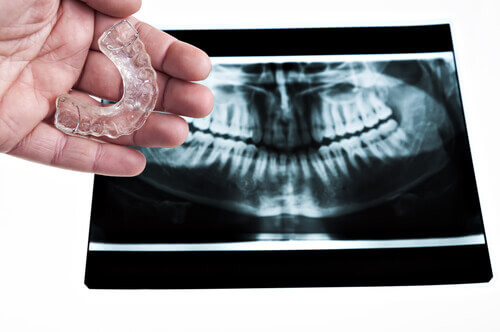

Du kan bruke tannbeskytter som hjelper tennene mot presset ved biting eller skjæring. Du kan også prøve en avslappende massasje i ansiktet, spesielt i områdene rundt kjeve, nakke og skuldre.